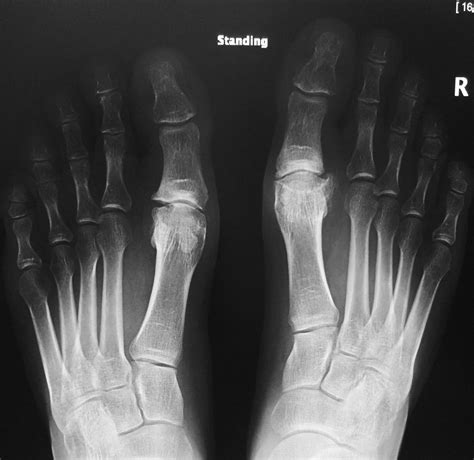

Experiencing stiffness, pain, or limited mobility in your foot can drastically impact your quality of life, especially when it stems from arthritis in big toe. This condition, medically known as hallux rigidus, is a form of degenerative arthritis that affects the metatarsophalangeal (MTP) joint—the base of your big toe. As the cartilage wears away, bone rubs against bone, leading to inflammation and the growth of bone spurs. Because we rely on the big toe for balance and propulsion during walking, running, or even standing, the discomfort associated with this condition can become debilitating if left unaddressed. Understanding the symptoms, causes, and treatment options is the first step toward reclaiming your mobility.

• Bone Spurs (Osteophytes): As the cartilage erodes, the body attempts to repair the joint by forming bone spurs on the top of the toe. These can create a noticeable bump that rubs against your footwear.